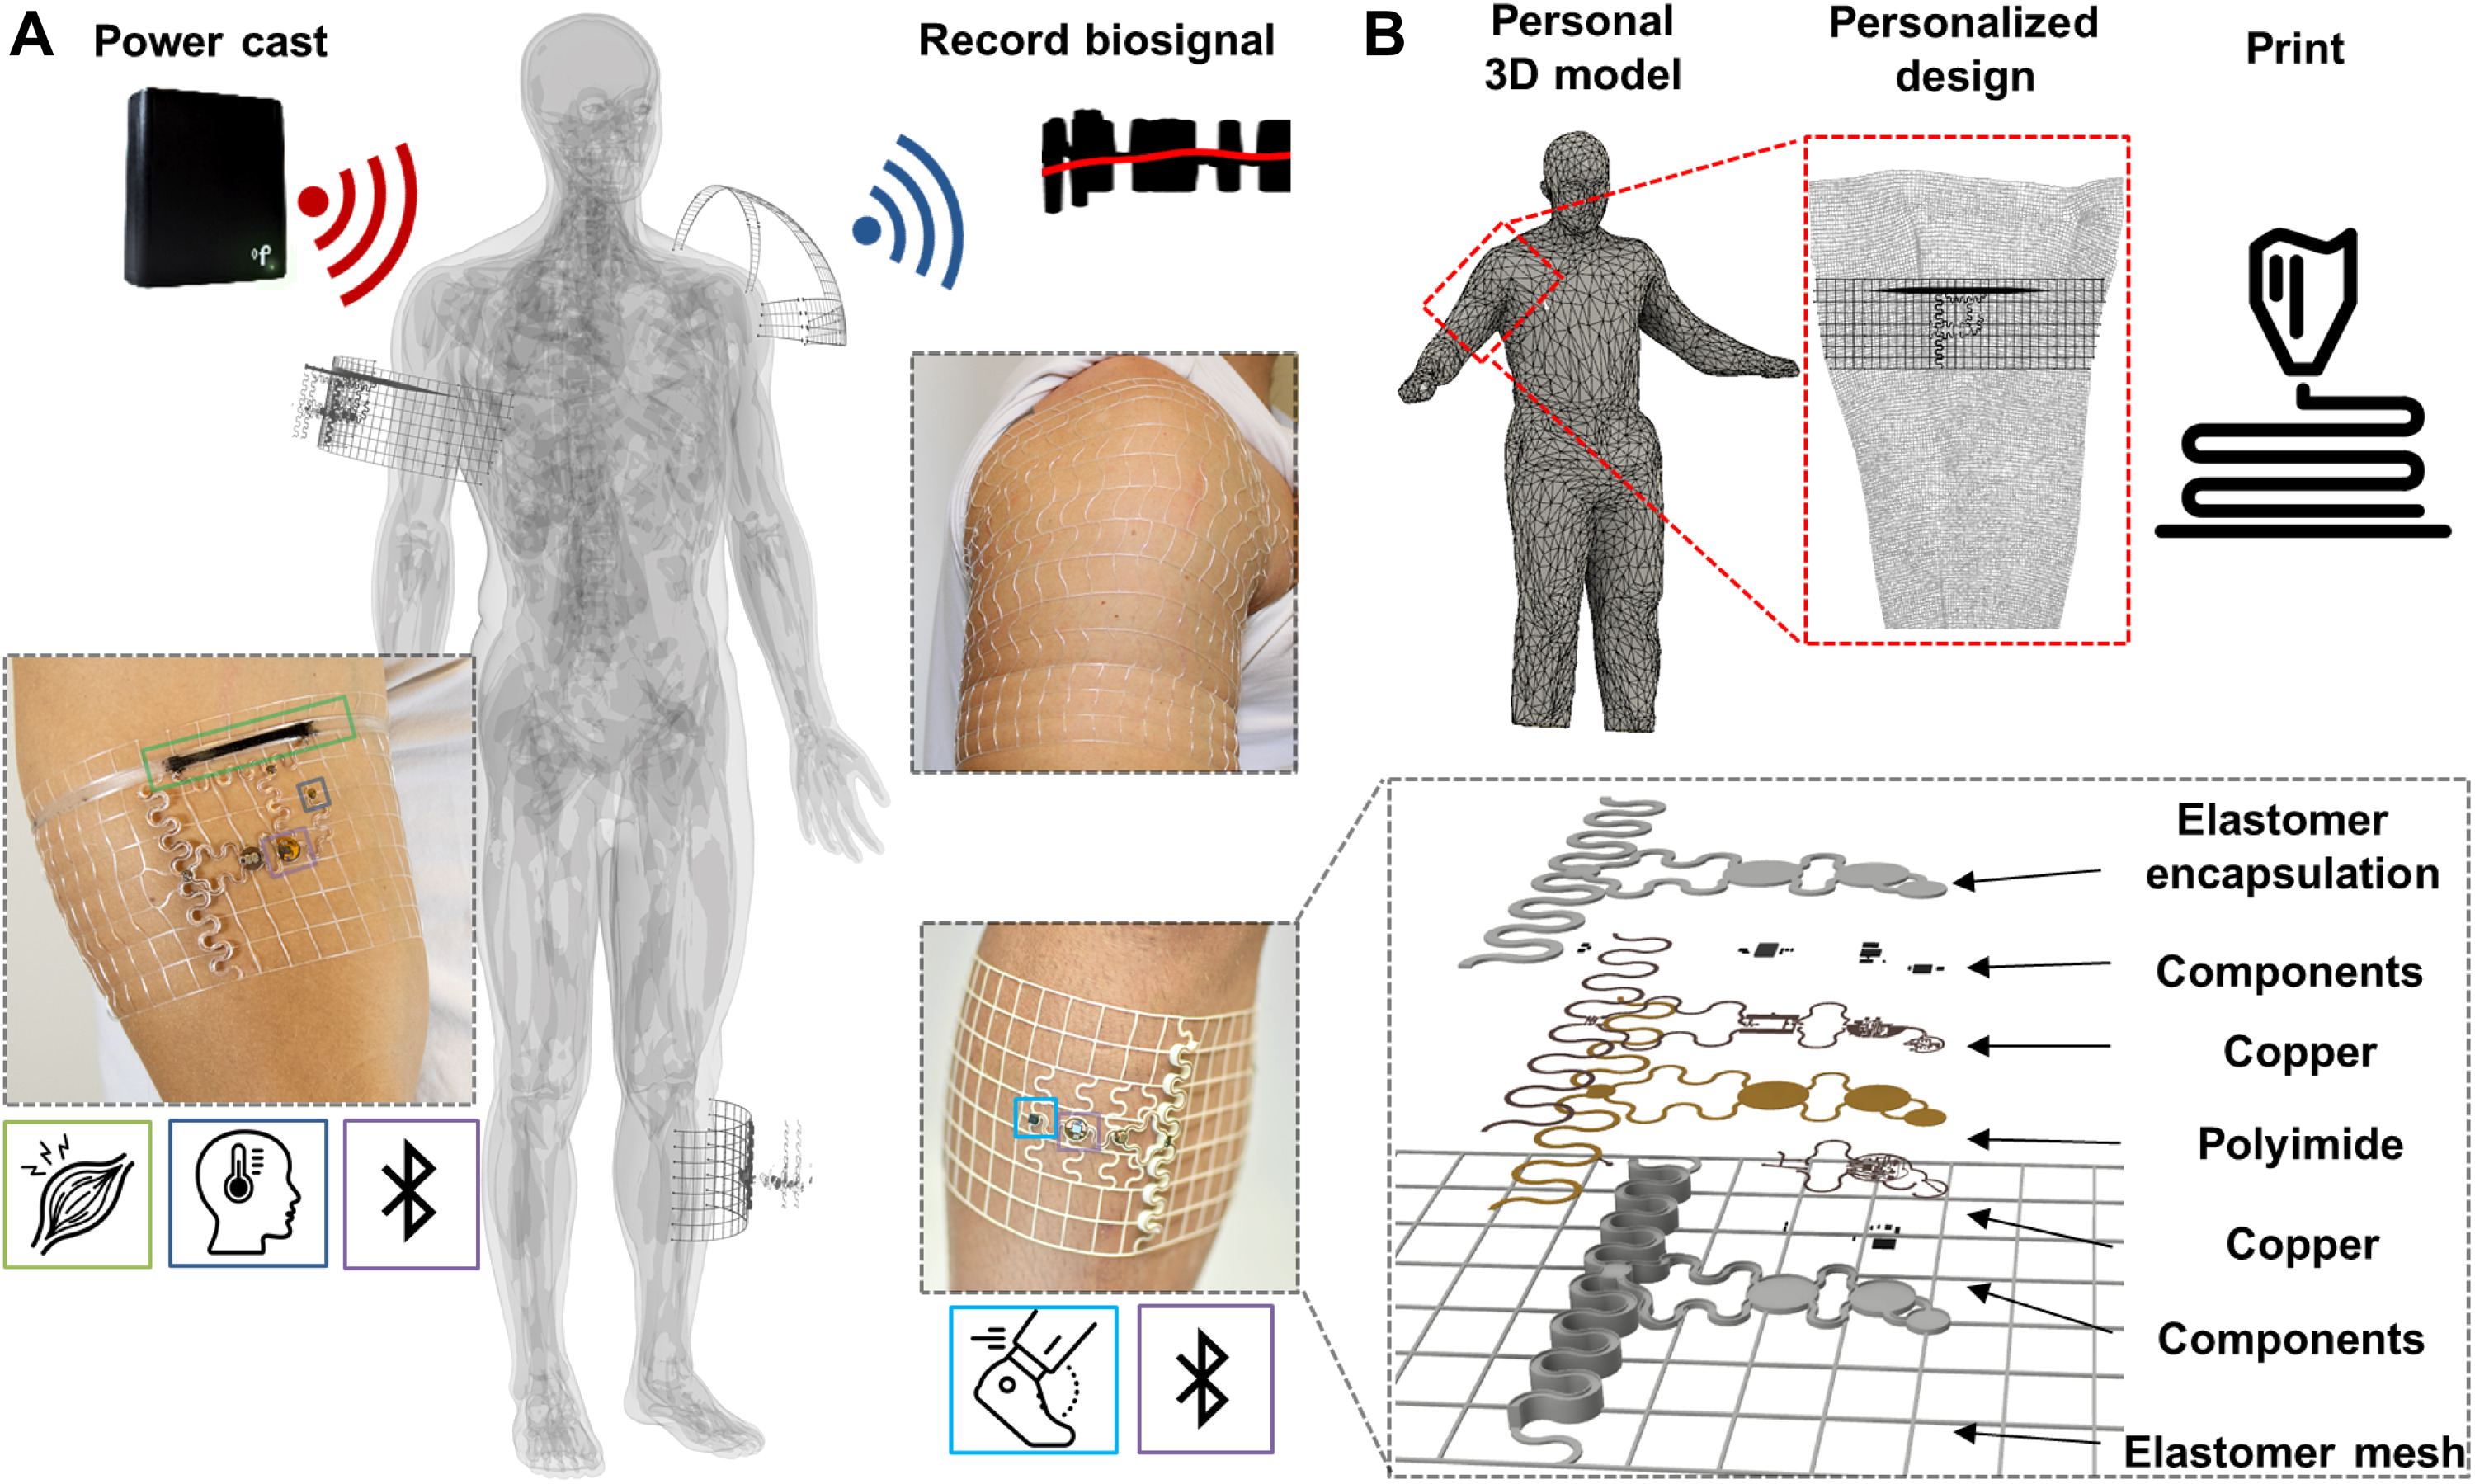

ARTICLE - Biosymbiotic, personalized, and digitally manufactured wireless devices for indefinite collection of high-fidelity biosignals

By TUCKER STUART, KEVIN ALBERT KASPER, CHRISTIAN IWERUNMOR, DYLAN THOMAS MCGUIRE, ROBERTO PERALTA, JESSICA HANNA, MEGAN JOHNSON, MAX FARLEY, THOMAS LAMANTIA, PAUL UDORVICH and PHILIPP GUTRUF | Science Advances | VOL. 7, NO. 41 | Oct 8, 2021

Digital medicine, the ability to stream continuous information from the body to gain insight into health status, manage disease, and predict onset health problems, is only gradually developing. Key technological hurdles that slow the proliferation of this approach are means by which clinical grade biosignals are continuously obtained without frequent user interaction. To overcome these hurdles, solutions in power supply and interface strategies that maintain high-fidelity readouts chronically are critical. This work introduces a previously unexplored class of devices that overcomes the limitations using digital manufacturing to tailor geometry, mechanics, electromagnetics, electronics, and fluidics to create unique personalized devices optimized to the wearer. These elastomeric, three-dimensional printed, and laser-structured constructs, called biosymbiotic devices, enable adhesive-free interfaces and the inclusion of high-performance, far-field energy harvesting to facilitate continuous wireless and battery-free operation of multimodal and multidevice, high-fidelity biosensing in an at-home setting without user interaction.

Video - Prof.Philipp Gutruf presents his lab where has developed 3-D printed, wearable devices that are powered wirelessly and which can seamlessly integrate with the shape of an individual’s body at Biomedical Engineering at the University of Arizona. The Lab is on the forefront of designing the next generation of biomedical devices for monitoring users’ health.

By TUCKER STUART, KEVIN ALBERT KASPER, CHRISTIAN IWERUNMOR, DYLAN THOMAS MCGUIRE, ROBERTO PERALTA, JESSICA HANNA, MEGAN JOHNSON, MAX FARLEY, THOMAS LAMANTIA, PAUL UDORVICH and PHILIPP GUTRUF | Science Advances | VOL. 7, NO. 41 | Oct 8, 2021

Digital medicine, the ability to stream continuous information from the body to gain insight into health status, manage disease, and predict onset health problems, is only gradually developing. Key technological hurdles that slow the proliferation of this approach are means by which clinical grade biosignals are continuously obtained without frequent user interaction. To overcome these hurdles, solutions in power supply and interface strategies that maintain high-fidelity readouts chronically are critical. This work introduces a previously unexplored class of devices that overcomes the limitations using digital manufacturing to tailor geometry, mechanics, electromagnetics, electronics, and fluidics to create unique personalized devices optimized to the wearer. These elastomeric, three-dimensional printed, and laser-structured constructs, called biosymbiotic devices, enable adhesive-free interfaces and the inclusion of high-performance, far-field energy harvesting to facilitate continuous wireless and battery-free operation of multimodal and multidevice, high-fidelity biosensing in an at-home setting without user interaction.

Video - Prof.Philipp Gutruf presents his lab where has developed 3-D printed, wearable devices that are powered wirelessly and which can seamlessly integrate with the shape of an individual’s body at Biomedical Engineering at the University of Arizona. The Lab is on the forefront of designing the next generation of biomedical devices for monitoring users’ health.